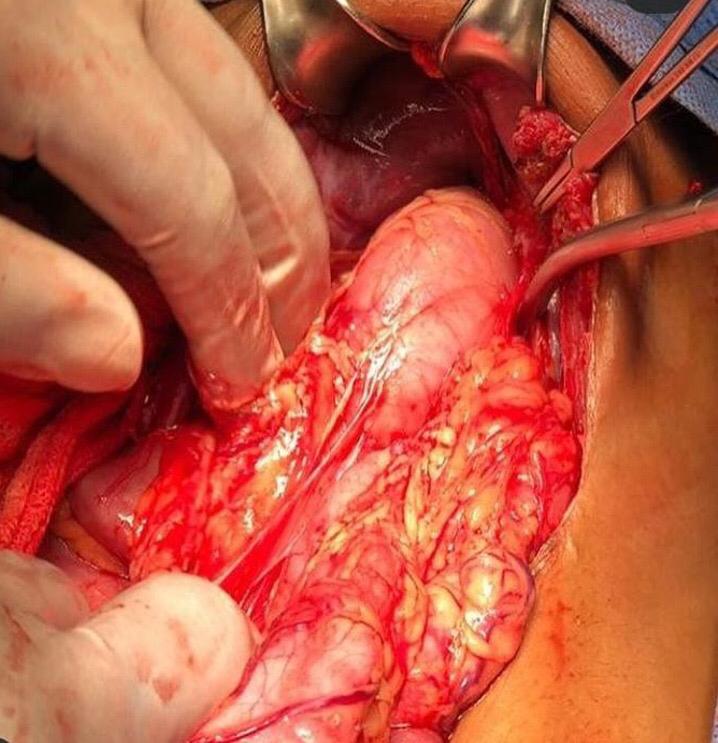

A este respecto, la doctora Robersy Pérez, Residente de 4to año, del Servicio Autónomo Hospital Universitario de Maracaibo (SAHUM) y perteneciente al Servicio de Cirugía Pediátrica “Dr. Darío Montiel Villasmil” presentó en su ponencia -durante las Jornadas Científicas del 61 Aniversario del SAHUM- el peligro mortal de la presencia de hernias en la población “se trata de un caso presentado en la institución basado en pacientes que presentan obstrucción (relacionado con el encarcelamiento; entre el músculo grande que separa el pecho del abdomen (defecto diafragmático) y las vísceras específicas, que se han herniado en el tórax) llegando incluso a la estrangulación”, explicó.

La hernia diafragmática postraumática puede aparecer tras un traumatismo del tórax y el abdomen contuso o penetrante. A causa de las lesiones coexistentes y la naturaleza silenciosa de la lesión diafragmática, el diagnóstico pasa en ocasiones desapercibido en fase aguda y puede manifestarse después, como un cuadro de obstrucción por los órganos encarcelados en el defecto diafragmático. En el adulto la hernia diafragmática traumática es una complicación conocida y poco común del trauma toraco- abdominal cerrado, que puede permanecer dormida por períodos prolongados y pasar inadvertido en un adulto mayor, haciendo que su diagnóstico diferido sea un verdadero reto para el médico. Además, puede manifestarse súbitamente, en el peor de los casos, con la muerte.

La doctora Robersy Pérez explicó el caso en cuestión “atendimos a un paciente de 9 años de edad, presentando dolor abdominal, tipo cólico, con 12 horas de evolución, insidioso generalizado, de leve a moderada intensidad, sin irradiación, con aumento de la medida que permite determinar la grasa acumulada en el cuerpo (perímetro abdominal) progresivo y vómitos, anteriormente en su etapa de recién nacido fue hospitalizado y tratado por meningitis, epilepsia controlada desde los 2 años de edad y con antecedentes de asma bronquial, siendo la última crisis a los 2 años”, detalló. Refirió que con el examen físico se encontró que sus condiciones clínicas del pequeño eran de cuidado: presentaba una moderada palidez cutánea y mucosa, deshidratación moderada, el abdomen estaba distendido y doloroso a la palpación de la zona abdominal. Detalló la doctora Robersy Pérez que en este paciente se encontraron con antecedentes quirúrgicos: extirpación del bazo (esplenectomía) más extracción del apéndice (apendicectomía) realizada en otro centro hospitalario y un trauma abdominal cerrado complicado, debido a arrollamiento vehicular hace años, donde se pasó desapercibido probablemente el defecto diafragmático “esto es raro encontrarlo en la edad pediátrica, pero a tener en cuenta en pacientes con accidentes de alto impacto”, dijo.

En este caso el desenlace fue exitoso sin consecuencias que lamentar “el paciente desde el primer día, transcurrió en condiciones clínicas estables, con dolor en sitio operatorio, presentando fiebre, sin embargo, mejorando hasta retirar el drenaje torácico y finalmente se le efectuó la restitución de tránsito intestinal, sin complicaciones hasta darle de alta”, concluyó. Ante esta patología se deben tener en cuenta los síntomas y a la menor sospecha; sea el caso en niños o adultos, debe acudir con el especialista para evitar consecuencias fatales.